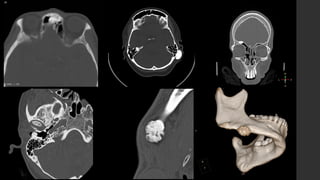

Osteoma osteoide.

• RX 

 Puede ser normal.

 Reacción perióstica sólida con

engrosamiento cortical.

 El nido es, a veces, visible como una

región radiolúcida circunscrita con un punto

esclerótico central.

• TC 

 El método de elección ya que es el mejor

para caracterizar la lesión.

 Nido hipodenso rodeado de hueso

esclerótico reactivo.

 Puede verse, dentro del nido, una

calcificación central.

• Centellografía 

 Captación típica focal central intensa con

anillo periférico de menor captación (signo

de doble densidad).

• US 

 Irregularidad cortical focalizada.

 Nido puede ser hipoecoico con refuerzo

acústico distal.

 Doppler  puede mostrar

hipervascularidad del nido.

• IRM 

 Es sensitiva más no específica para

identificar el nido.

 La intensidad de señal del nido y el realce

que presenta, es variable en todas las

secuencias.

Greenspan A, Jundt G, Remagen W. Differential diagnosis in orthopaedic oncology. Lippincott Williams & Wilkins. (2006)